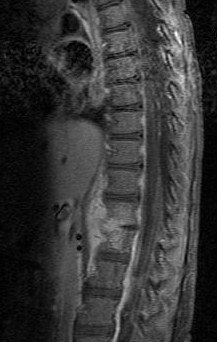

La discitis es un proceso inflamatorio que afecta al disco intervertebral y a la superficie de los cuerpos vertebrales.

Diskitis is a rare primary infection of the nucleus pulposus which may spread to adjacent vertebral bodies. It is acquired by hematogenous seeding, direct spread from vertebral osteomyelitis, and direct trauma, including surgery and spinal manipulation.